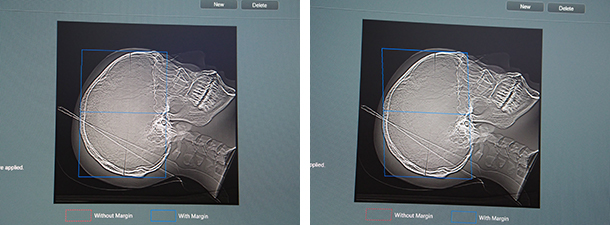

ワークフロー向上のコンセプトSynergyDriveにおいては,自動位置決めの“AutoPose”が,これまでの肺野に加えて頭部にも対応した。スキャノグラムから解剖を自動認識し,撮影範囲を自動設定する。頭部では,OMライン,SMライン,RBラインの3つの基準に対応し,マージンも任意に設定できる。

“AutoPose”が頭部にも適応。OMライン(左)やSMライン(右)などの基準ラインを自動で設定する。